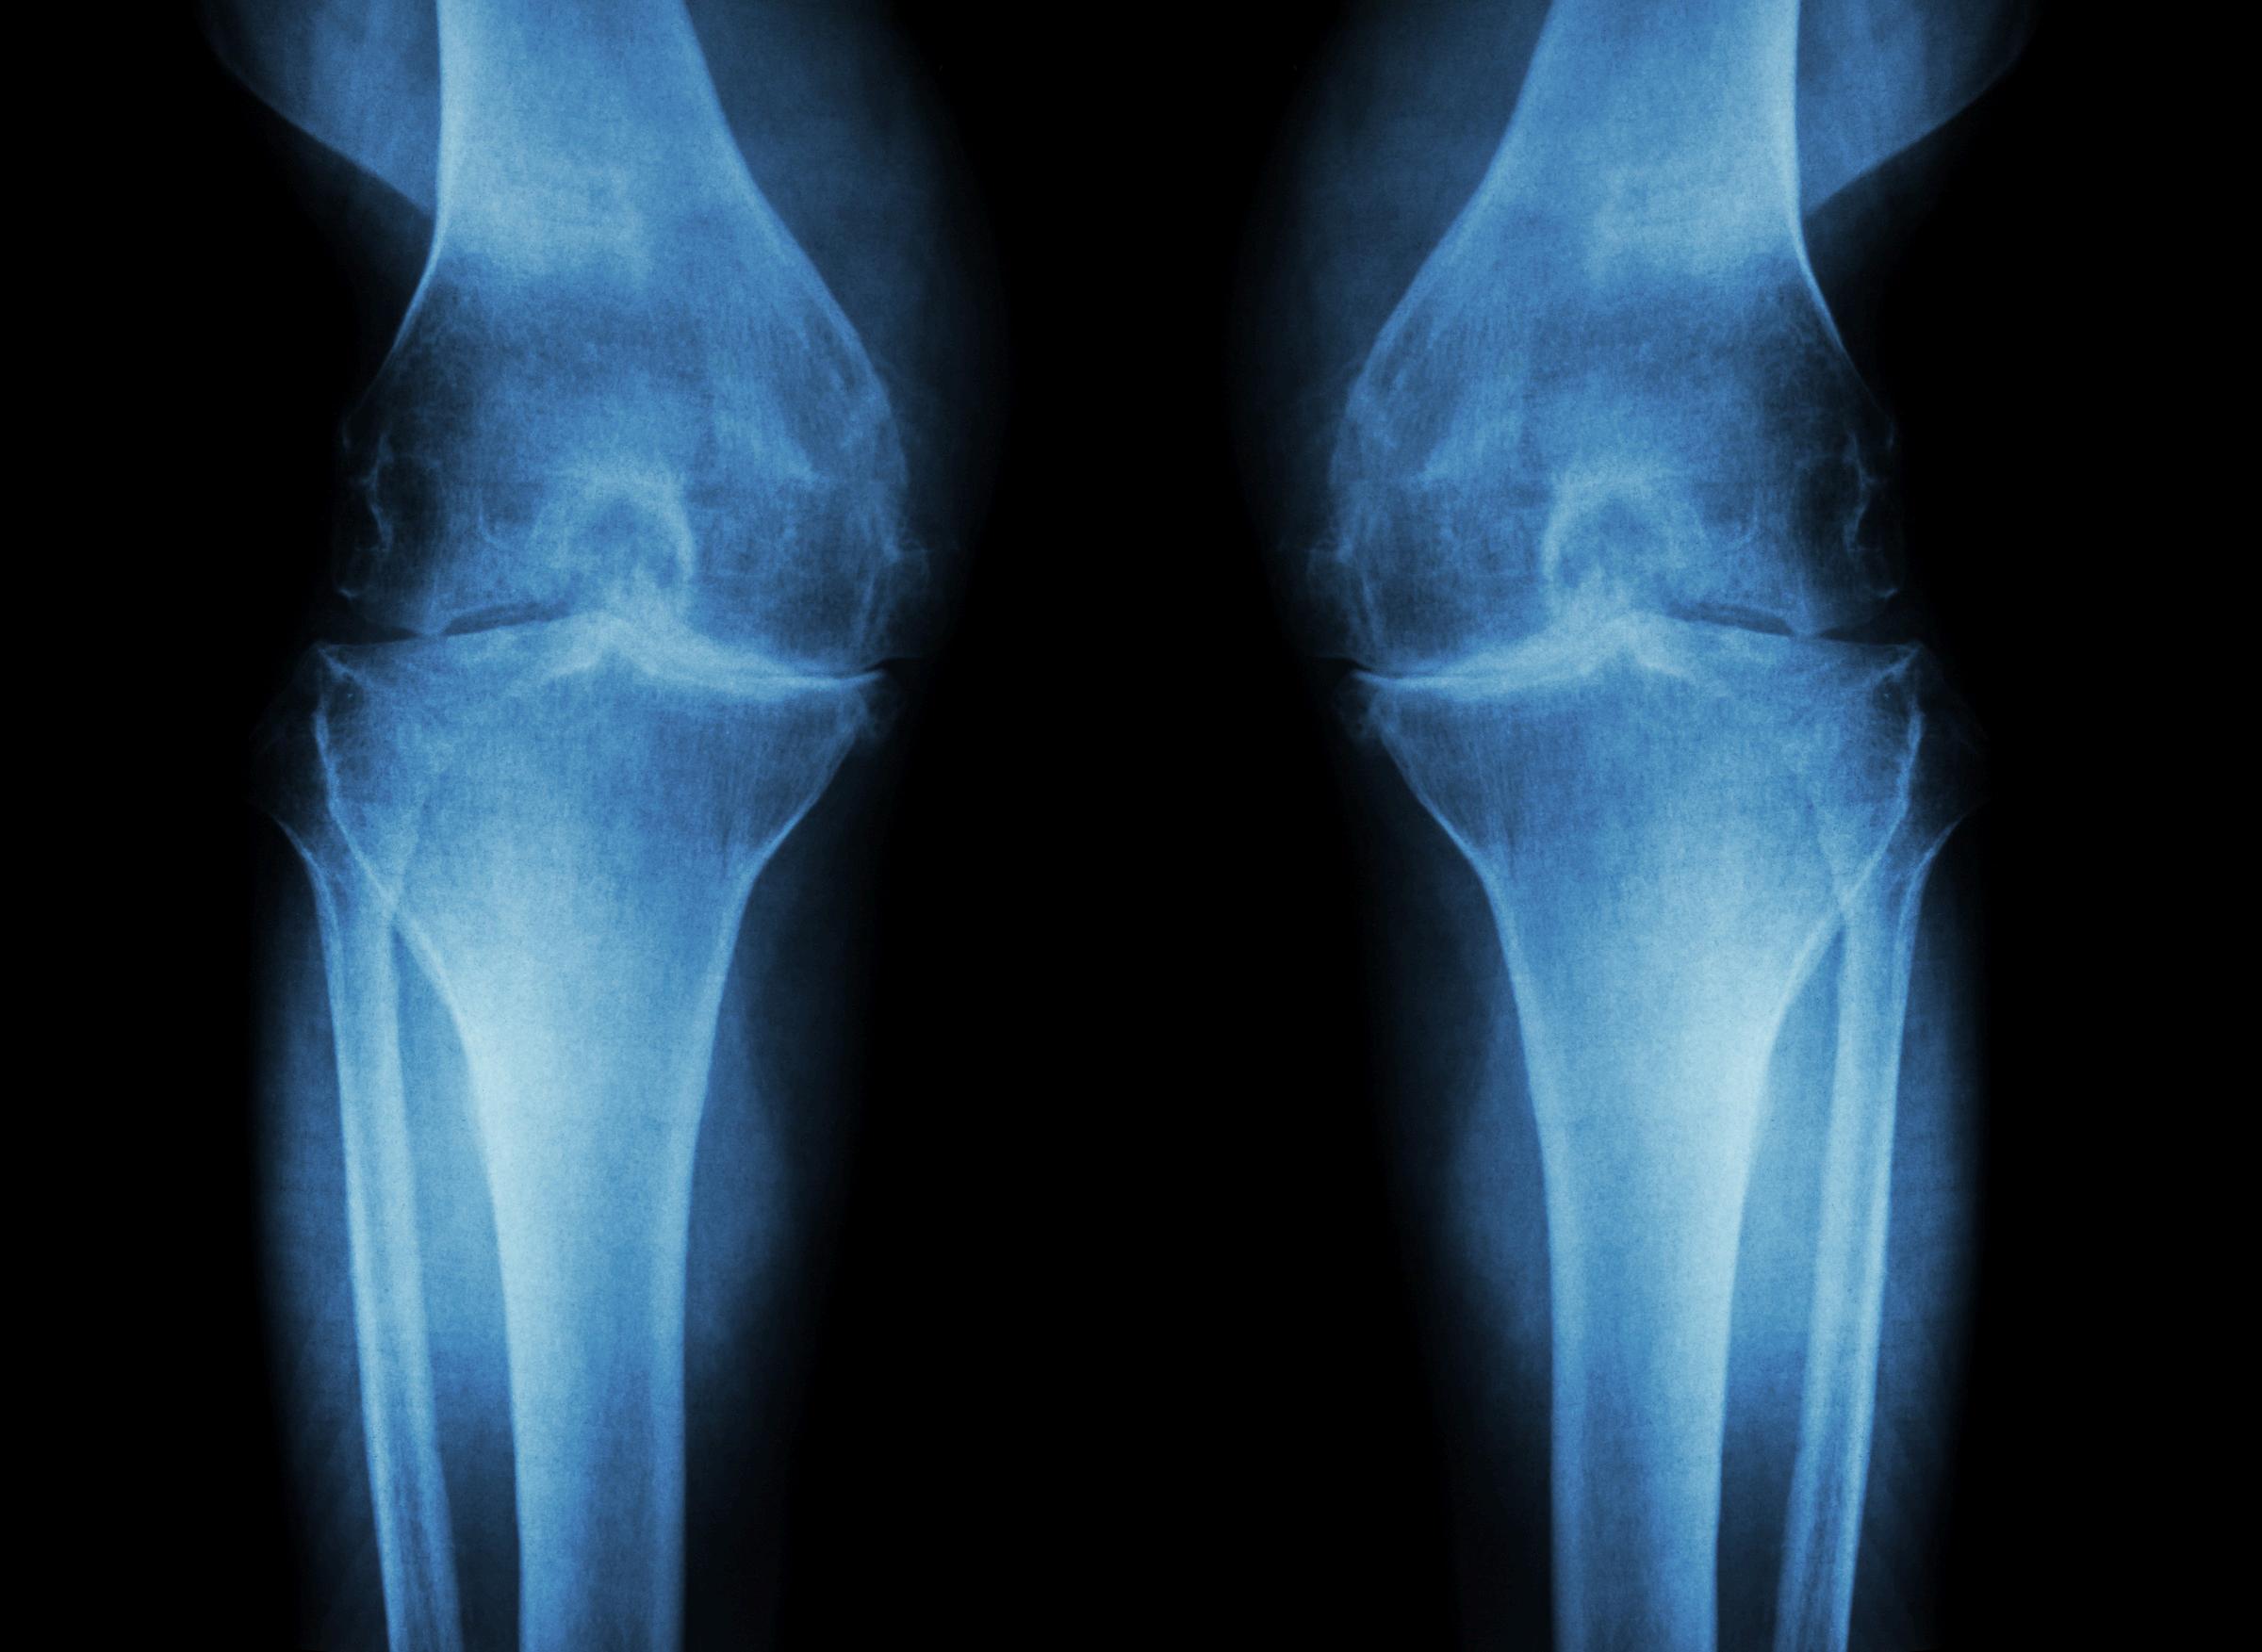

ARTROSIS DE RODILLA: UN DESAFÍO CRECIENTE PARA LA SALUD ARTICULAR

La artrosis de rodilla, también conocida como osteoartritis de rodilla, es una enfermedad degenerativa que afecta a millones de personas en todo el mundo Caracterizada por el desgaste progresivo del cartílago que recubre las superficies articulares de la rodilla, esta condición puede llevar a dolor, rigidez e incapacidad funcional, afectando significativamente la calidad de vida de quienes la padecen.

Causas y Factores de Riesgo

Las causas de la artrosis de rodilla son multifactoriales. Entre los factores de riesgo más comunes se encuentran la edad avanzada, el sobrepeso, las lesiones previas en la rodilla, la genética y ciertas actividades laborales o deportivas que implican un uso repetitivo de la articulación. El envejecimiento natural del cuerpo reduce la capacidad de los tejidos para repararse, lo que, combinado con el desgaste mecánico, conduce al deterioro del cartílago.

Síntomas y Diagnóstico

Los síntomas de la artrosis de rodilla incluyen dolor que empeora con la actividad y mejora con el reposo, rigidez matutina, hinchazón y una disminución en el rango de movimiento Con el tiempo, puede desarrollarse una deformidad visible en la articulación. El diagnóstico se basa en la evaluación clínica, el historial médico y estudios de imagen como radiografías o resonancias magnéticas, que permiten observar el grado de desgaste y la afectación de los tejidos circundantes

El manejo de la artrosis de rodilla se centra en aliviar los síntomas y mejorar la función articular. Las opciones de tratamiento incluyen cambios en el estilo de vida, como la pérdida de peso y el ejercicio regular para fortalecer los músculos que sostienen la rodilla. Además, se utilizan medicamentos antiinflamatorios y analgésicos para controlar el dolor y la inflamación. En algunos casos, las inyecciones intraarticulares de corticosteroides o ácido hialurónico pueden proporcionar alivio temporal.

Para aquellos pacientes que no responden a los tratamientos conservadores, la cirugía puede ser una opción. Las intervenciones quirúrgicas van desde la artroscopia, que permite limpiar la articulación, hasta la osteotomía y la sustitución total de rodilla, que implica reemplazar la articulación dañada con una prótesis

Prevención y Futuro

La prevención de la artrosis de rodilla incluye mantener un peso saludable, realizar ejercicio de bajo impacto, y proteger las rodillas de lesiones mediante el uso de equipo adecuado y técnicas correctas en deportes y actividades laborales La investigación continúa buscando nuevas terapias y tratamientos que puedan no solo aliviar los síntomas, sino también detener o revertir el proceso degenerativo. En resumen, la artrosis de rodilla representa un desafío significativo para la salud pública, pero con un enfoque adecuado en prevención, diagnóstico temprano y tratamiento integral, es posible mejorar la calidad de vida de los pacientes afectados